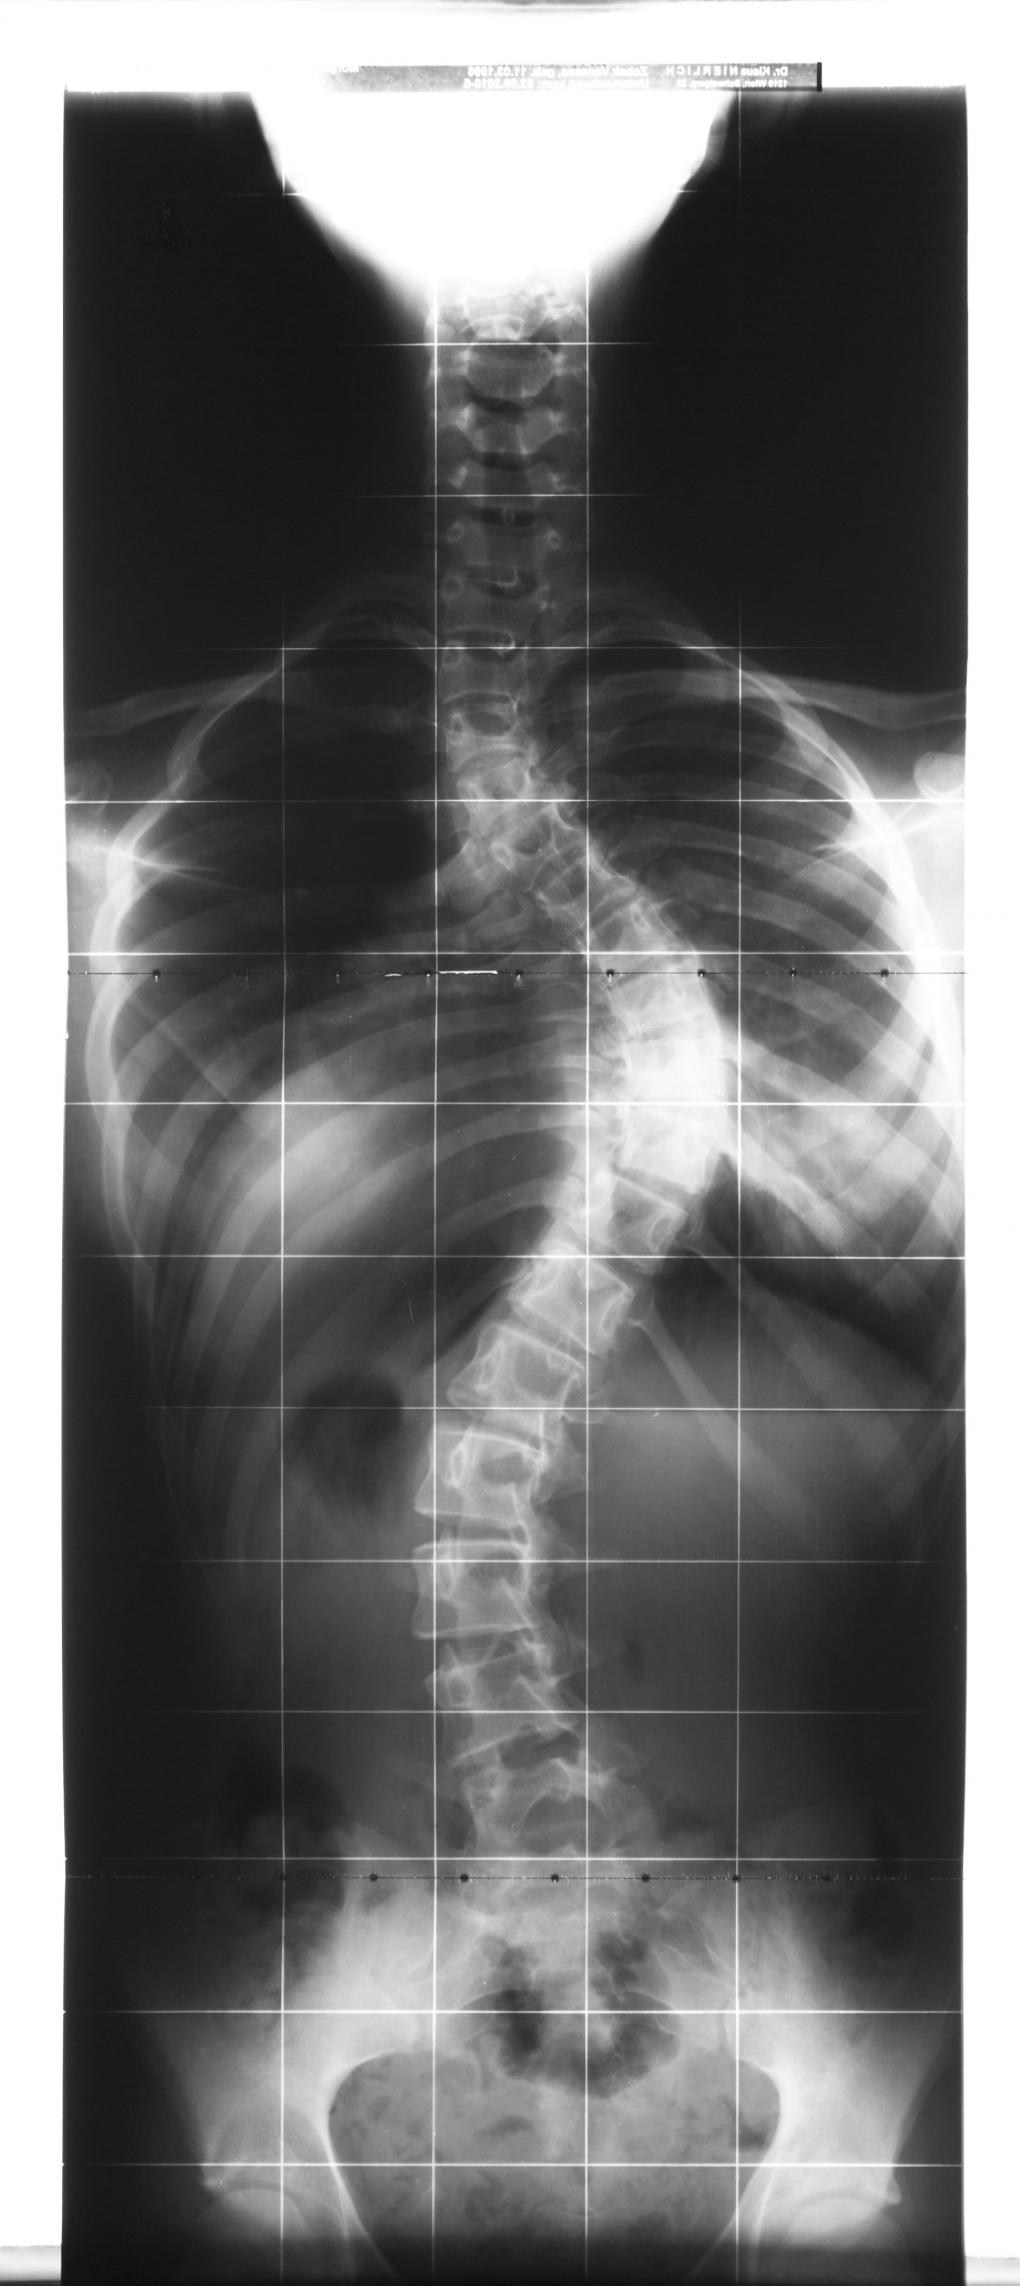

Skoliose ist eine Seitverbiegung der Wirbelsäule bei gleichzeitiger Verdrehung der Wirbelkörper. Dadurch kommt es zum Längenverlust und zu einer Verformung des Rumpfes.

Zusätzlich kommt es bei einer typischen Skoliose zur Ausbildung eines Flachrückens im Bereich der Brustwirbelsäule.

Sicherheit über das Vorhandensein einer Skoliose gibt letztlich das Röntgenbild, das die/der Ärztin/Arzt anordnet. Die Krümmung wird dann vermessen, und der Schweregrad der Skoliose anhand einer Skala bestimmt.